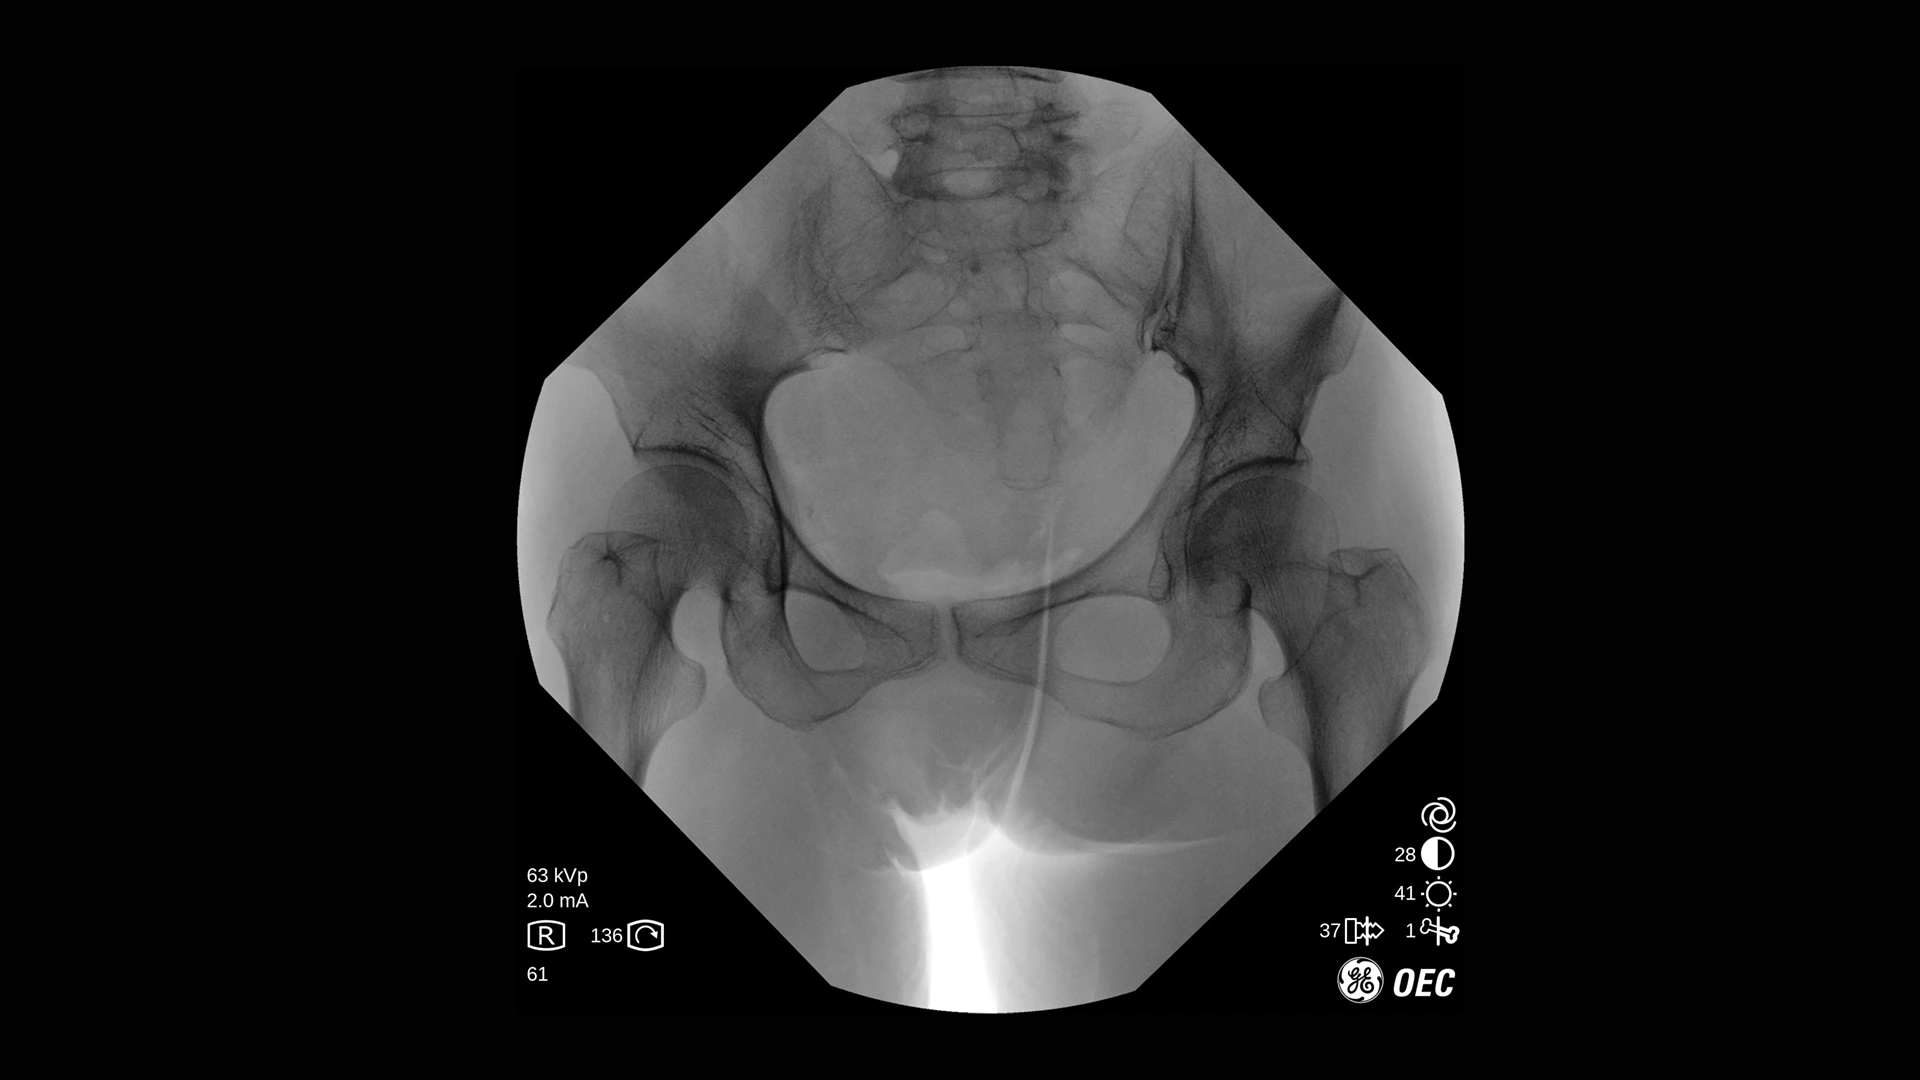

GE Healthcare OEC One CFD относится к классу мобильных рентгеновских аппаратов с С-образной дугой, в которых все ключевые узлы — излучатель, детектор, монитор и панель управления — объединены в единую компактную конструкцию. КМОП-плоскопанельный детектор и фирменная цепочка обработки Clear View обеспечивают высокую детализацию изображения в широком спектре клинических задач: от рутинных травматолого-ортопедических вмешательств до эндоваскулярных процедур и сложной спинальной хирургии. Интеллектуальные алгоритмы подавления помех от металлоконструкций, автоматической оптимизации окна и уровня, а также режимы увеличения позволяют уверенно визуализировать мелкие структуры, проводники и импланты без существенного роста дозовой нагрузки.

- Режимы рентгеноскопии, цифрового снимка и субтракционной ангиографии для интраоперационного контроля хода вмешательств.

- Специализированные клинические профили для ортопедии, спинальной хирургии, общей хирургии, урологии, сосудистых и болевых процедур.

| Непрерывная рентгеноскопия | Постоянное наблюдение области интереса в режиме реального времени для контроля хода вмешательства и позиционирования инструментов. |

| Низкодозовая рентгеноскопия | Снижение лучевой нагрузки при длительных рентгеноскопических исследованиях и повторных проверках положения имплантов. |

| Импульсная рентгеноскопия | Формирование изображения серией импульсов для уменьшения дозы при сохранении достаточной детализации. |

| Режим цифрового снимка (Digital Spot) | Получение высокодетализированного статического кадра для оценки критически важных анатомических структур. |